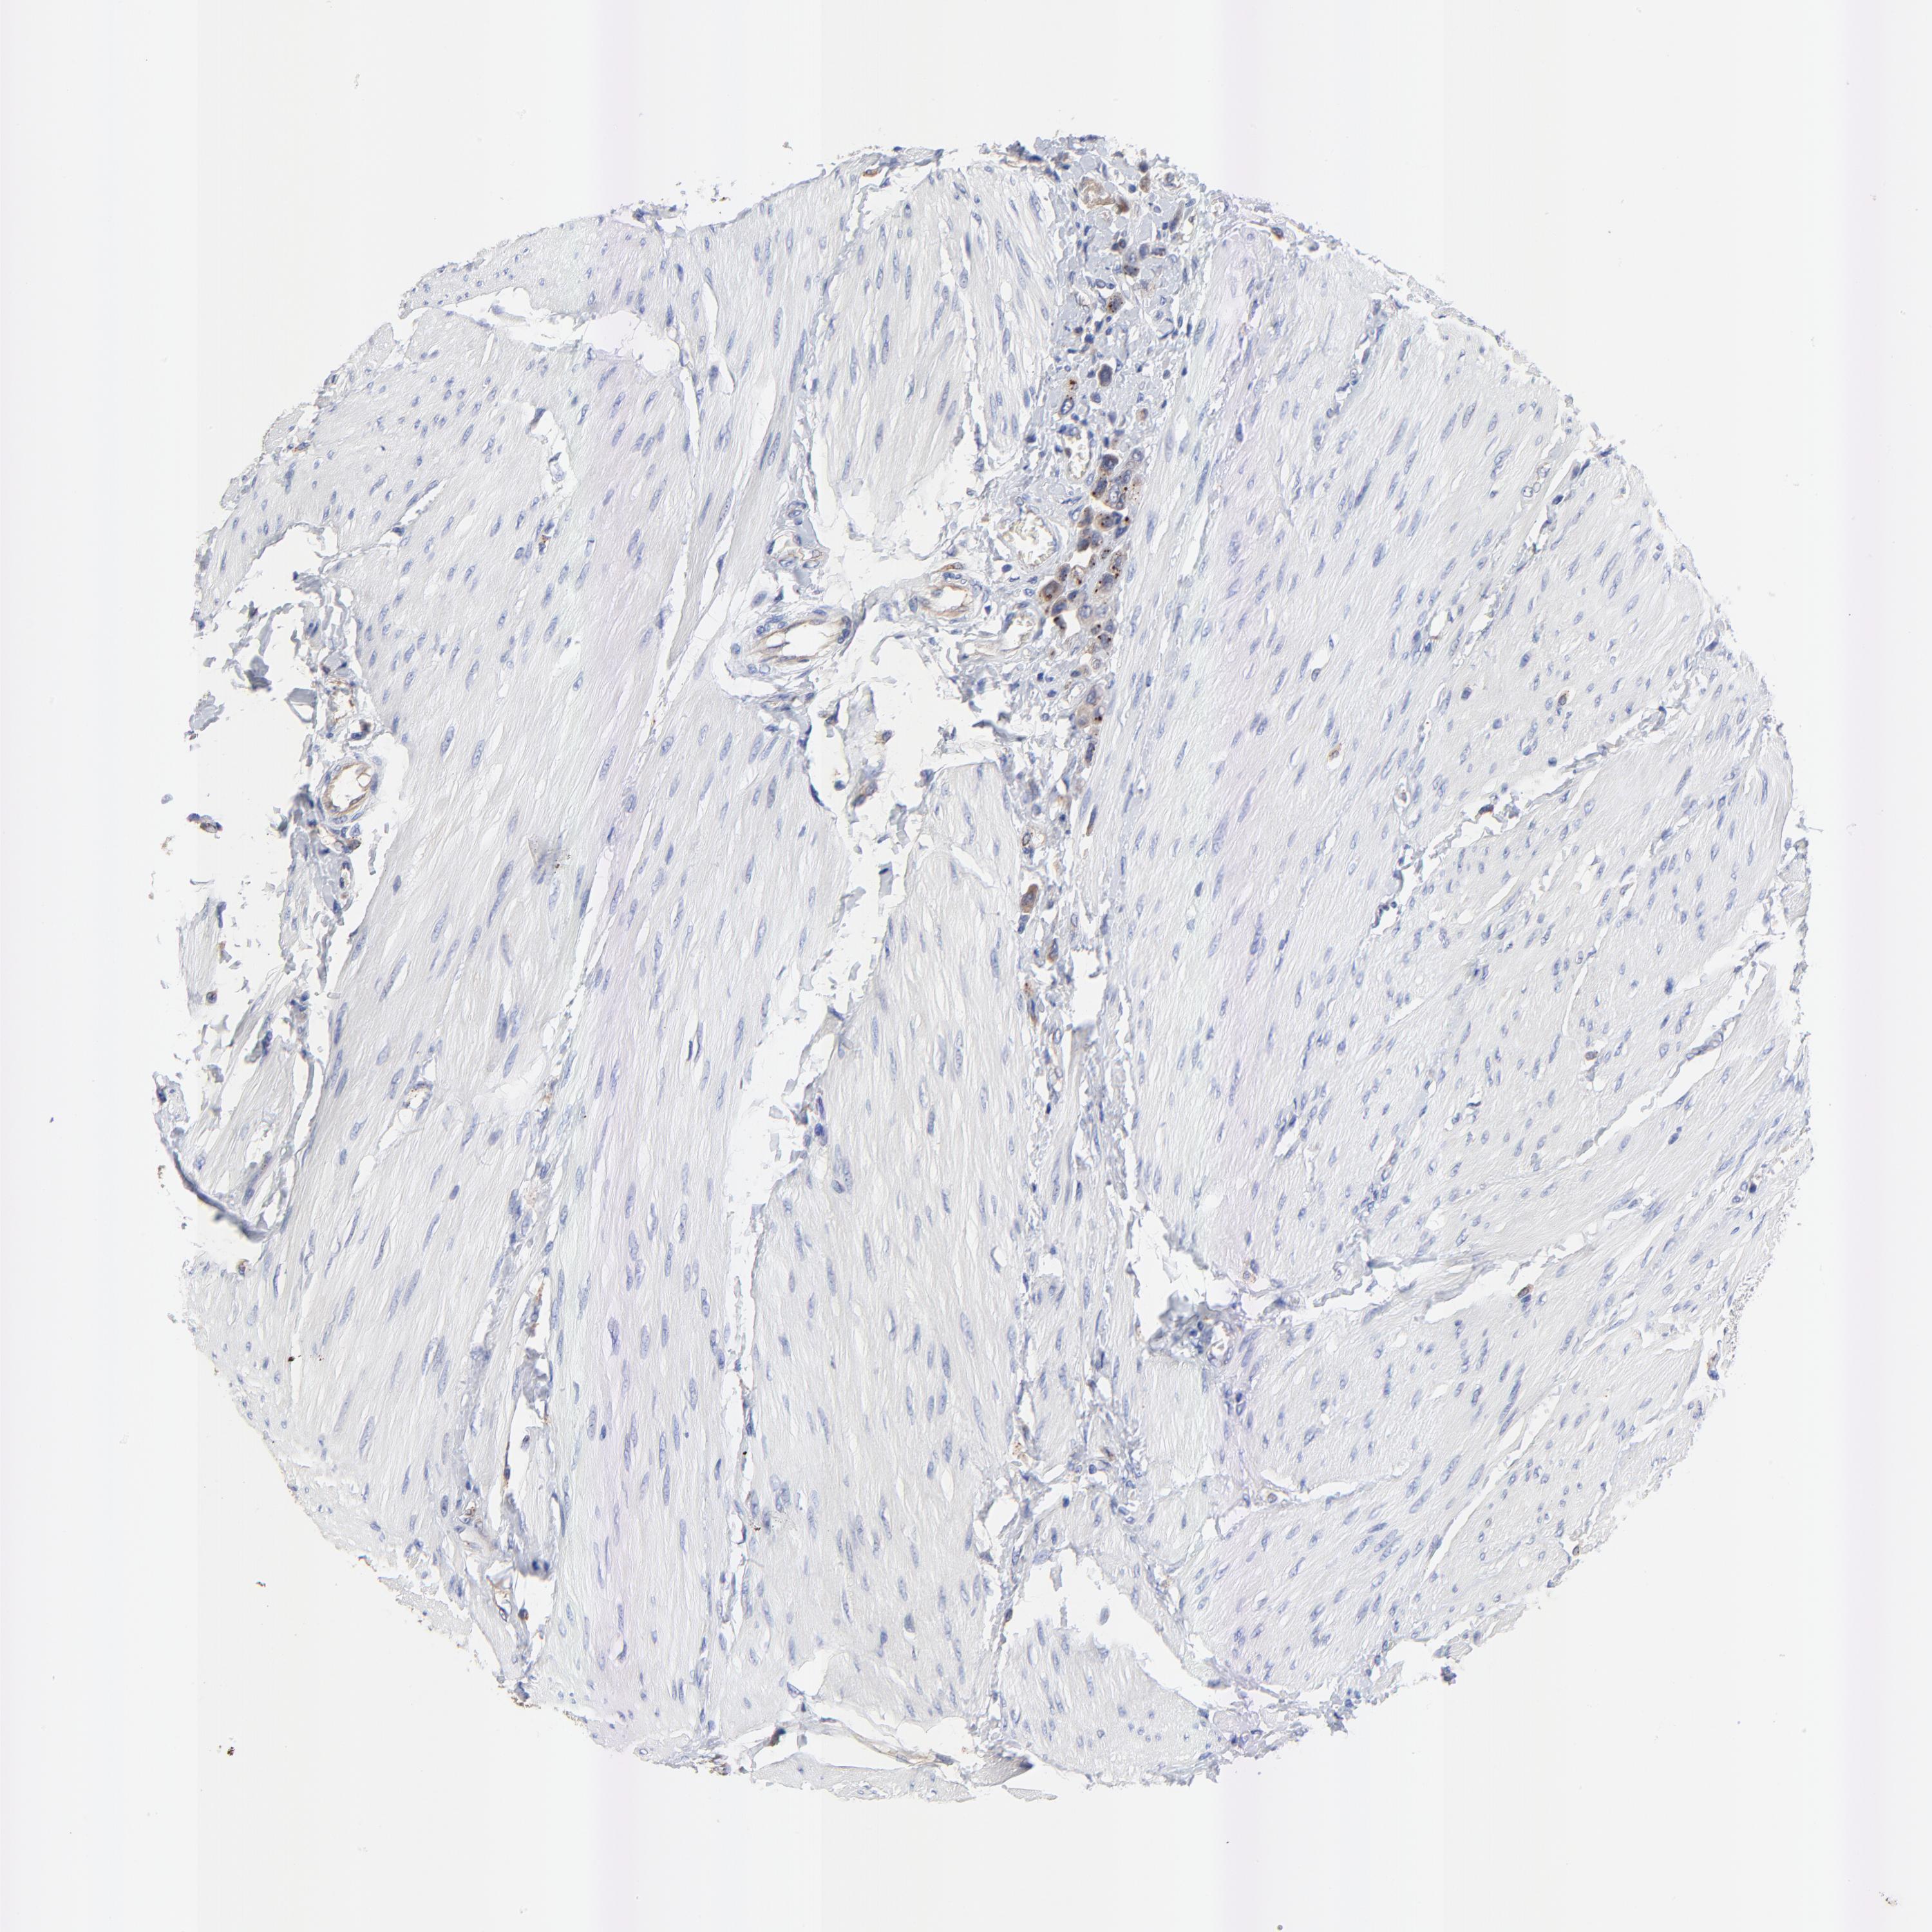

UROTHELIAL CANCER - Protein expressioni

A mouse-over function shows sample information and annotation data. Click on an image to view it in a full screen mode. Samples can be filtered based on level of antibody staining by selecting one or several of the following categories: high, medium, low and not detected. The assay and annotation is described here.

Antibody stainingi

Antibody staining in the annotated cell types in the current human tissue is reported as not detected, low, medium, or high, based on conventional immunohistochemistry profiling in selected tissues. This score is based on the combination of the staining intensity and fraction of stained cells.

Each image is clickable and will lead to virtual microscopy that enables deeper exploration of all samples and also displays staining intensity scores, fraction scores and subcellular localization as well as patient and tissue information for each sample.

Antibody HPA003240

Staining

High

Medium

Low

Not detected

Intensity

Strong

Moderate

Weak

Negative

Quantity

>75%

75%-25%

<25%

None

Location

Nuclear

Cytoplasmic/membranous

Cytoplasmic/membranous,nuclear

Urothelial carcinoma, High grade

Urothelial carcinoma, Low grade